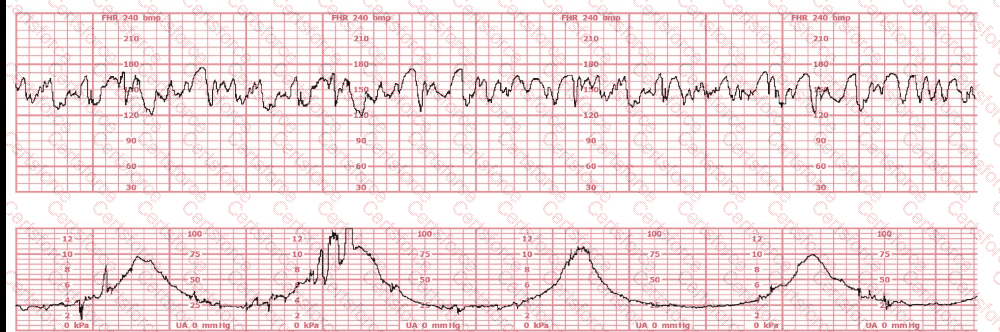

Questions # 9:

A woman (G1, P0) at 41-weeks gestation presents to OB triage to rule out labor. Her cervical exam is 1 cm/50%/-2. Membranes are intact. She would like to go home if not in labor. Based on this tracing, which represents the last two hours, the best approach is:

Question # 9

A.

B.

C.